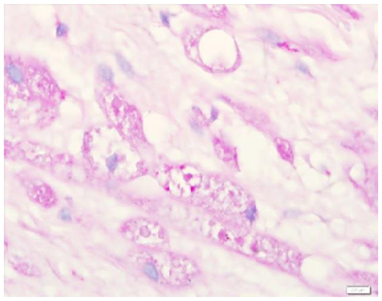

An excision biopsy specimen from a mass at elbow of 26 years old female patient was received for histopathological examination. The clinical impression was of ‘benign soft tissue tumor’. The specimen was received in 10% formalin in one container. On gross examination, it was a 1.5 x 1 x 0.5 cm well-circumscribed, grey-tan mass, without skin component. The cut surface was solid homogenous and no necrotic or hemorrhagic areas were found on it. The microscopic examination revealed a circumscribed encapsulated lesion composed of round to polygonal to spindle shaped cells with eosinophilic granular cytoplasm and centrally placed small nuclei (Figure 1 & Figure 2). Cells were arranged in intersecting bundles and mixed with fibrous connective tissue (Figure 3). The Intralesional peripheral nerve bundles surrounded by the lesional cells were seen (Figure 4). No significant mitoses or cells with cross striation, significant inflammatory infiltrate or necrosis were seen. IHC showed positive results for S100 (Figure 5) and neuron-specific Enolase (NSE) (Figure 6). Smooth muscle actin (SMA) (Figure 7) and Myogenin were negative. CEA was focally positive. Periodic acid-schiff (PAS) stain showed PAS positive intracytoplasmic granules (Figure 8). The lesion was completely excised with <1mm safety margin. Focal entrapment of the adjacent fatty tissue was observed. Based on the above mentioned findings, diagnosis of granular cell tumor (GCT) was made.

Granular cell tumor (GCT) is a rare tumor (Figure 1) and rarely diagnosed prior to histopathological examination of (Figure 2) the biopsy or excised specimen. The GCTs are usually poorly circumscribed and non-encapsulated. However, circumscribed encapsulated GCT can occur, especially in the skin and subcutaneous tissue. Reported cases of encapsulated GCTs are also present in the medical literature. The morphology of GCTs on H&E is easy to identify and it should be supported by PAS stain and IHC. PAS positive cytoplasmic granularity is a characteristic feature of the GCTs. GCTs are positive for S100, NSE, NK1-C3, vimentin, CD57 and CD68.1,4-7 The GCTs are non immunoreactive for epithelial, muscle, endothelial and glial cell markers. CEA positivity in some GCTs is a false positive result most likely due to non-specific cross reacting antigen in GCTs.